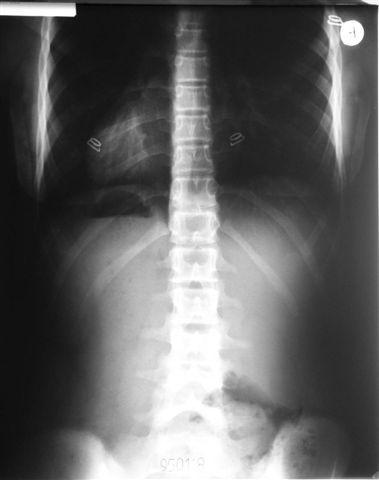

Na radiogramach przebieg leczenia jednej z moich pacjentek.